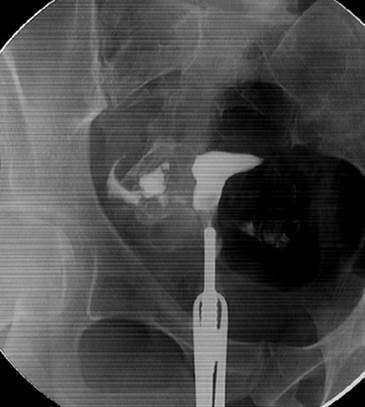

Paciente de 34 años al momento de su primera consulta de fertilidad en centro privado, con una gesta y un aborto, antecedente de legrado a los 21 años, antecedentes familiares no contributorios, e infertilidad de 3 años. La pareja masculina tenía 4 hijos mayores. Ninguna sospecha inicial de TBC. El ultrasonido transvaginal era normal. Se solicitó el plan básico de estudios para infertilidad: laboratorio, histerosalpingografía (HSG), y espermatograma. Al regresar a consulta control para evaluar todos los estudios solicitados, llamó la atención las imágenes de la HSG, destacando, en la cavidad uterina, imágenes de defecto y, en las trompas, imágenes de trompas arrosariadas con un barrido trabecular persistente durante todo el estudio que otorgan la sospecha para un importante factor tuboperitoneal, a decartar TBC, las cuales se reevaluaron con otros médicos (Figura 1).

Figura 1 imagen de histerosalpingografía de la paciente del caso 1. Se destaca la imagen arrosariada, especialmente de la trompa izquierda. El Cotte es positivo, bilateral, con barrido trabecular irregular.